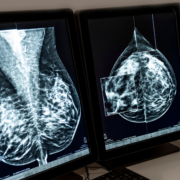

- Dense breasts. Dense breast tissue appears solid white on mammograms and may be more challenging to see through. In most cases, a 3D Screening Mammogram will see suspicious abnormalities that could be breast cancer, but additional imaging may be recommended on a case-by-case basis.

- Abnormality. If something appears suspicious, additional imaging or a biopsy of that area may be needed.